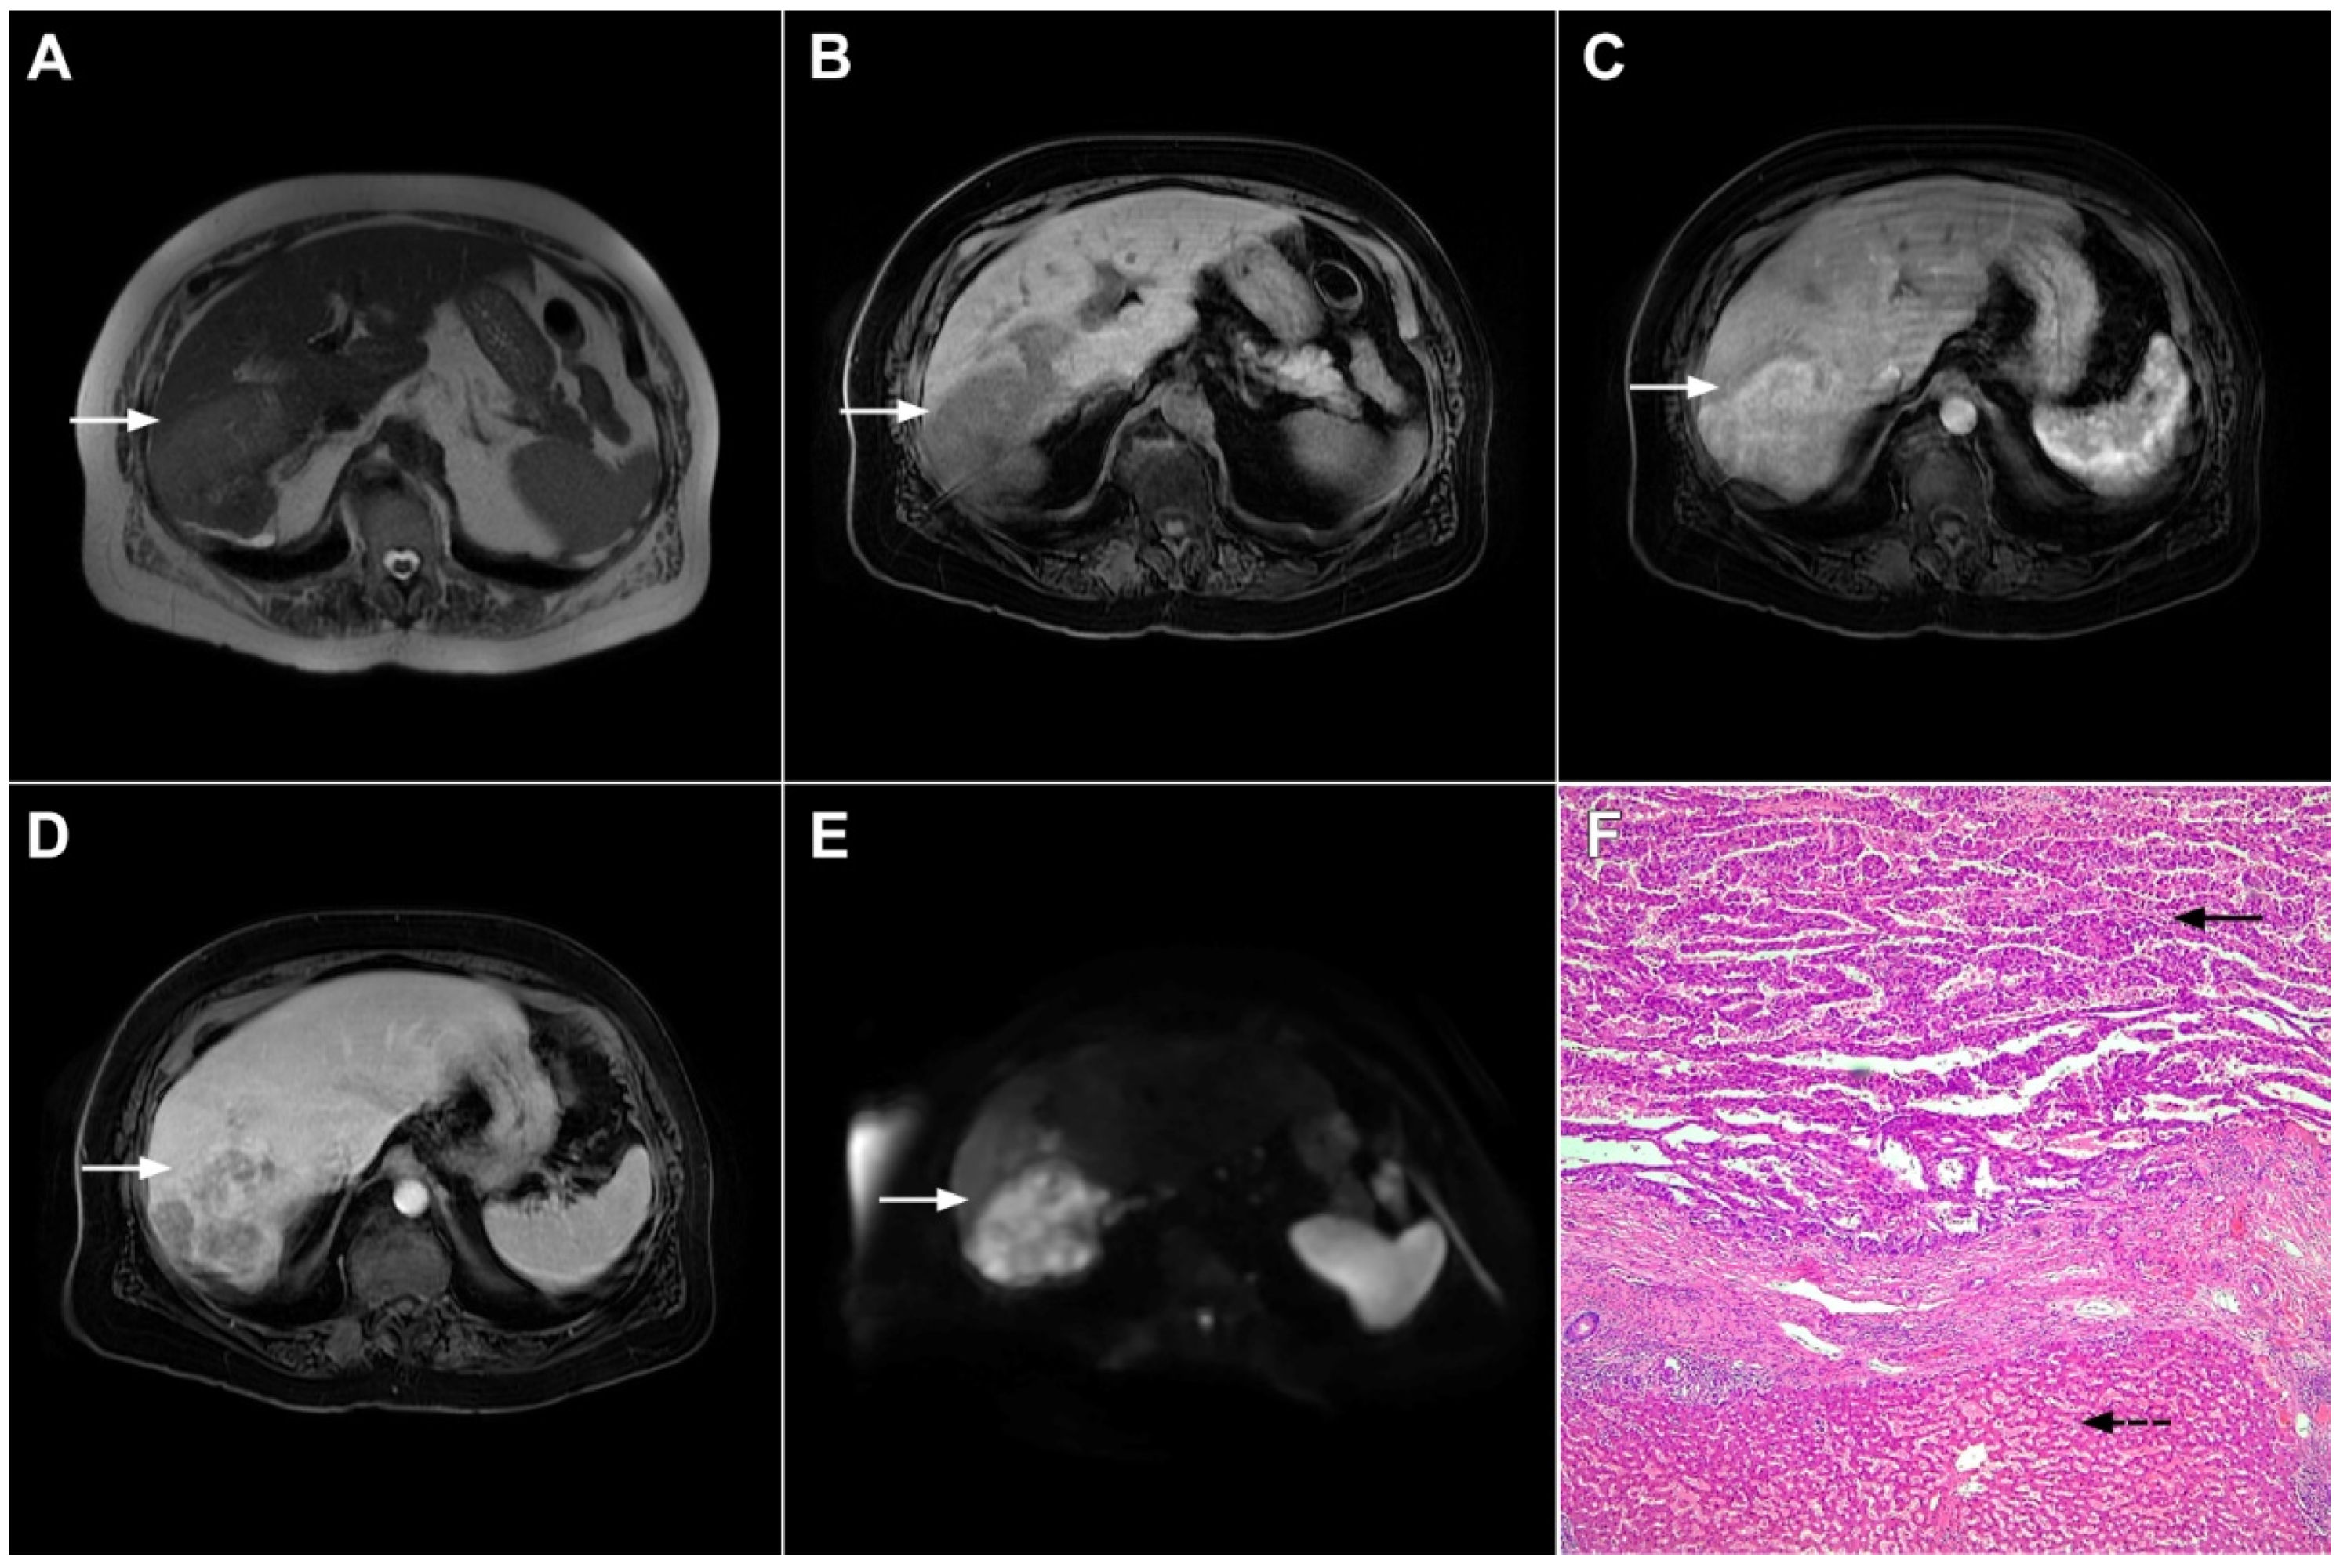

3.2. Malignant Lesions

3.2.1. Solitary Hypovascular Liver Metastasis

3.2.2. Atypical Forms of Hepatocellular Carcinoma

Scirrhous HCC